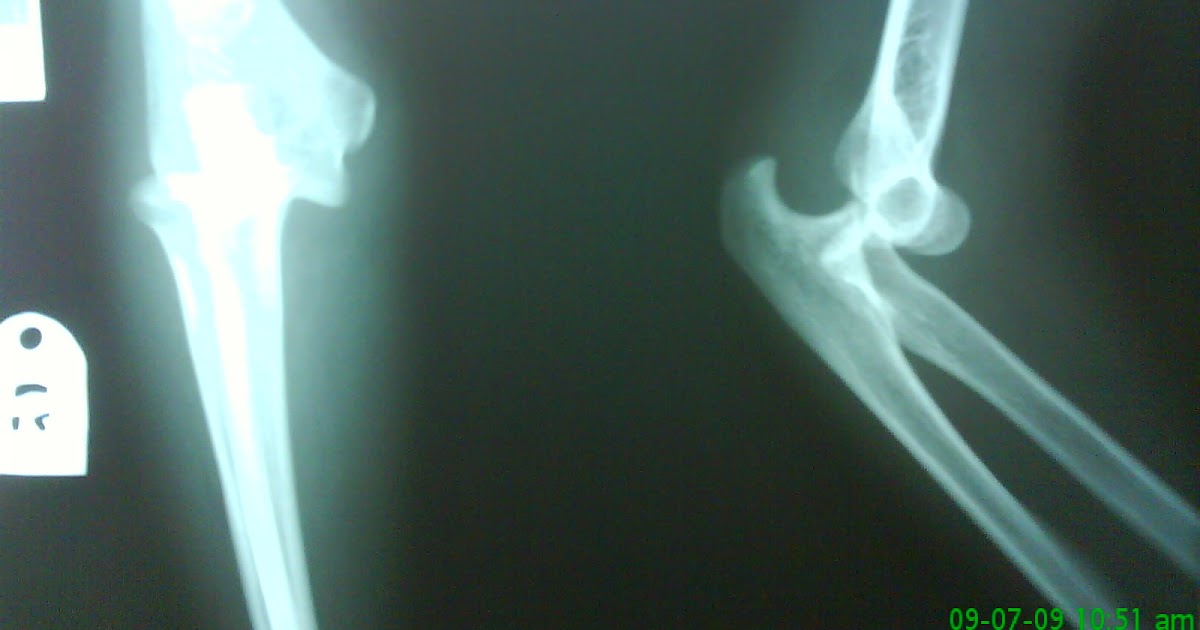

Elbow injury case study

Elbow injury case study picture This image illustrates Elbow injury case study.